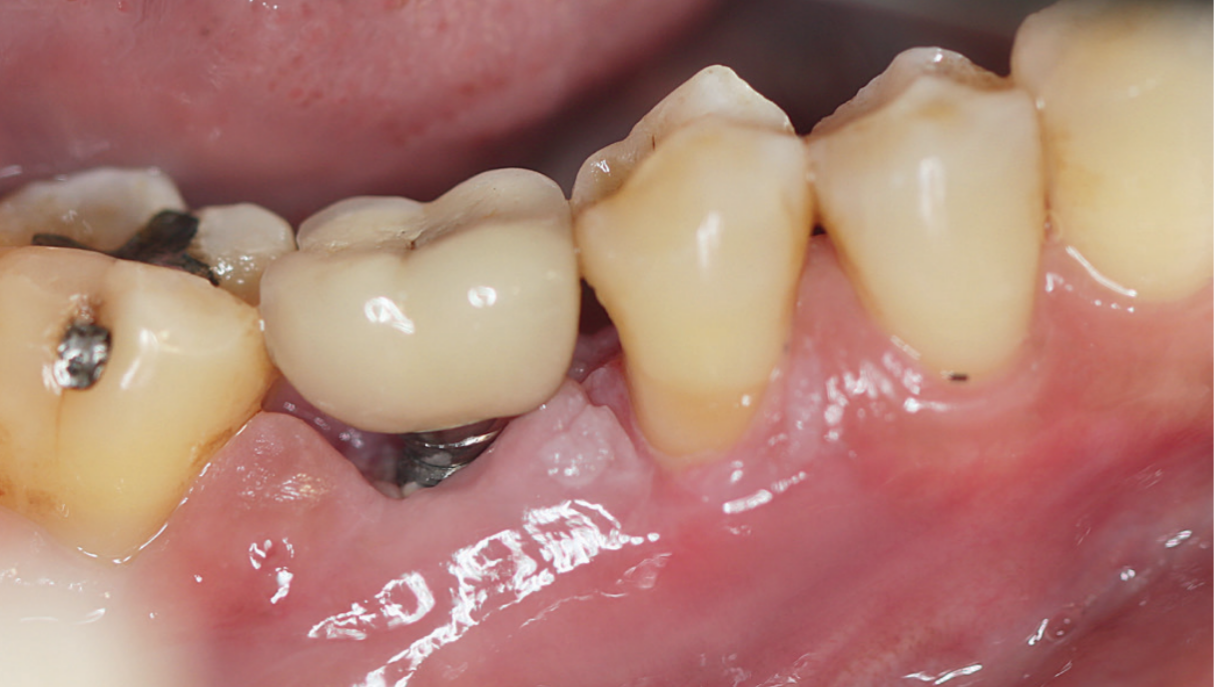

Ja iekaisumu laikus nediagnosticē un neuzsāk atbilstošu ārstēšanu, tas var progresēt līdz periimplantītam – hroniskam iekaisumam ap zobu implantu, kura laikā ap implantu pakāpeniski notiek kaula zudums, visbiežāk sākot no implanta kakliņa zonas. Periimplantīts lielākoties attīstās lēni un sākotnēji noris bez sāpēm, kas šo slimību padara īpaši bīstamu, jo pacients ilgstoši var nepamanīt problēmas esamību. Slimībai progresējot, smagākos gadījumos var novērot smaganu atkāpšanos, kā arī implanta kustīgumu.

Ko pacients nejūt, bet ārsts redz apskates laikā

Viena no lielākajām periimplantīta problēmām ir tā, ka pacients to bieži nejūt. Nav izteiktu sāpju, nav traucējoša diskomforta, nav "signāla", kas liktu nekavējoties vērsties pie ārsta.

Apskates laikā ārsts var pamanīt:

- Asiņošanu, kas redzama tikai zondējot, vai strutu izdalīšanos ap implantu.

- Smaganu kabatu padziļināšanos ap implantu.

- Agrīnas kaula līmeņa izmaiņas radioloģiskajos izmeklējumos.